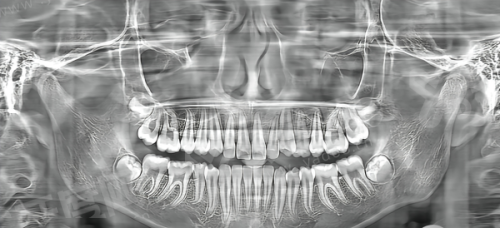

1、采用“3D口腔扫描+AI方案设计”技术,通过iTero口内扫描仪3分钟获取牙齿数据,生成3D矫正动画,患者可提前预览矫正效 果,方案沟通更直观。

2、矫正方案:张敏医生采用“拔牙+滑动直丝弓技术”,先拔除4颗智齿腾出空间,通过轻力牵引调整虎牙位置,每4周复诊一次,期间配合咬胶训练增强咬肌力量。

2、矫正方案:李伟医生设计“上颌扩弓+前牙压低”方案,共佩戴42副隐形牙套,每2周更换一副,配合种植钉辅助压低前牙,同时指导患者练习“微笑训练”改善露龈问题。

2、矫正方案:王芳医生采用“FR-Ⅲ功能矫治器”,每晚佩戴8小时,配合面部肌功能训练,引导下颌后退,促进上颌骨发育。